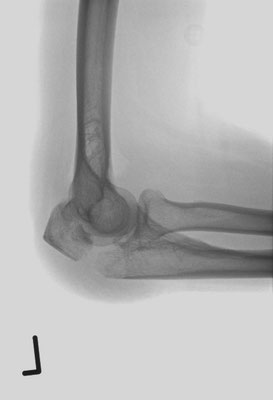

Ellenbogennaher Oberarmbruch/suprakondyläre Oberarmfraktur

Diese Brüche gehen häufig mit einer erheblichen Zertrümmerung des Knochens einher. In den meisten Fällen ist auch die Gelenkfläche betroffen, so dass eine operative Rekonstruktion erforderlich ist. Wie bei allen gelenknahen Knochenbrüchen besteht die Aufgabe darin, ein sehr kurzes Knochenfragment an dem Schaftknochen zu befestigen und die Gelenkfläche stufenlos wieder herzustellen. In der Standardtechnik werden dabei zwei Platten benutzt. Dabei geben insbesondere die winkelstabilen Titanplatten optimale Möglichkeiten um die kleinen Knochenteile stabil zu befestigen.

Ist allerdings die Gelenkfläche so stark zerstört, dass eine Rekonstruktion nicht möglich ist, bietet sich bei Patienten in höherem Lebensalter die Implantation einer Ellenbogenprothese an. Mit dieser ist eine gute Funktion zu erreichen.